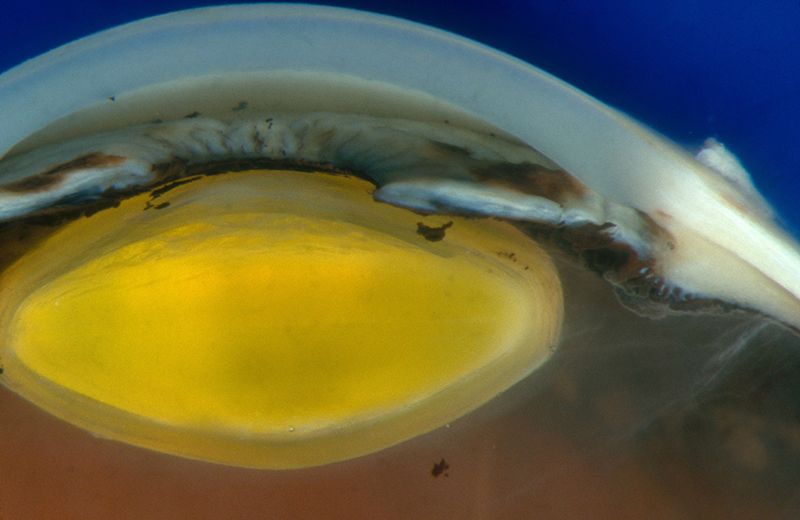

Учёные из Страны восходящего солнца впервые в истории провели операцию по пересадке роговицы, которая была создана в лабораторных условиях.

Офтальмологи из Осакского университета создали орган с применением стволовых клеток. Это значит, что значительно снизился риск отторжения трансплантата, поскольку раньше для подобных операций использовались доноры.

Также использование донорского материала сопровождается целым рядом специфических сложностей, из-за которых только в Японии есть более чем полторы тысячи людей, ожидающих операции. Использование искусственных роговиц, выращенных из стволовых клеток, может решить эту проблему.

Эффективность метода врачи доказали, проведя операцию на добровольце – 40-летней жительнице Японии. Женщина страдала от заболевания под названием ретикулярная дисгенезия роговичного эпителия, которое проявляется в виде нарушенной прозрачности роговицы.

В конце июля в её левый глаз пересадили полученный из клеток донора тонкий слой ткани. Женщину выписали из больницы через месяц. Её зрение с момента процедуры улучшилось.